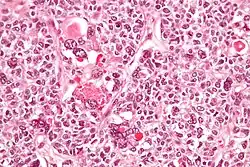

Micrograph of a juvenile granulosa cell tumour with hyaline globules. H&E stain. | |

Juvenile granulosa cell tumors can be distinguished from adult granulosa cell tumors on histology by their abundant, eosinophilic cytoplasm; primitive, highly mitotic nuclei in polygonal cells; and disorganized follicles.[12][13]